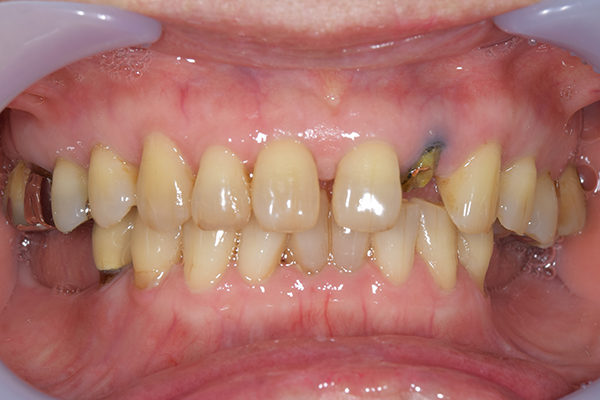

前歯が折れて当院にいらっしゃいました。 過去に下の入れ歯を作ったが、合わなくなってずっと入れ歯をいれていらっしゃらない患者様でした。 これは奥歯で噛むことができないため、前歯で噛むことを繰り返したために、負担に耐えられなくなった前歯が折れてかぶせ物ごと 外れてしまったのだと考えられます。 痛くない、違和感の少ない、下の入れ歯を作ることがこの方のゴールであると考えられました。

右上のインプラント周囲炎で、その部分が痛いという患者様でした。 また奥歯で噛むことが難しかったため、前歯を使用することが多くなり、 前歯が前よりも前に出てきていることも気になっていらっしゃいました。

インプラント部以外にも歯周病が進行していましたので、歯周病の治療を行いました。 残念ながらインプラントと、1本の歯が残せなかったため抜歯を行いました。 その後、前歯の出っ張りを修正することと入れ歯の安定を図るため、残っている歯を全てかぶせ物にしていくことになりました。 写真中央は抜歯後に入れた治療用の入れ歯になります。 抜歯後歯ぐきが安定しましたら、入れ歯とかぶせ物の型取りを行いました。